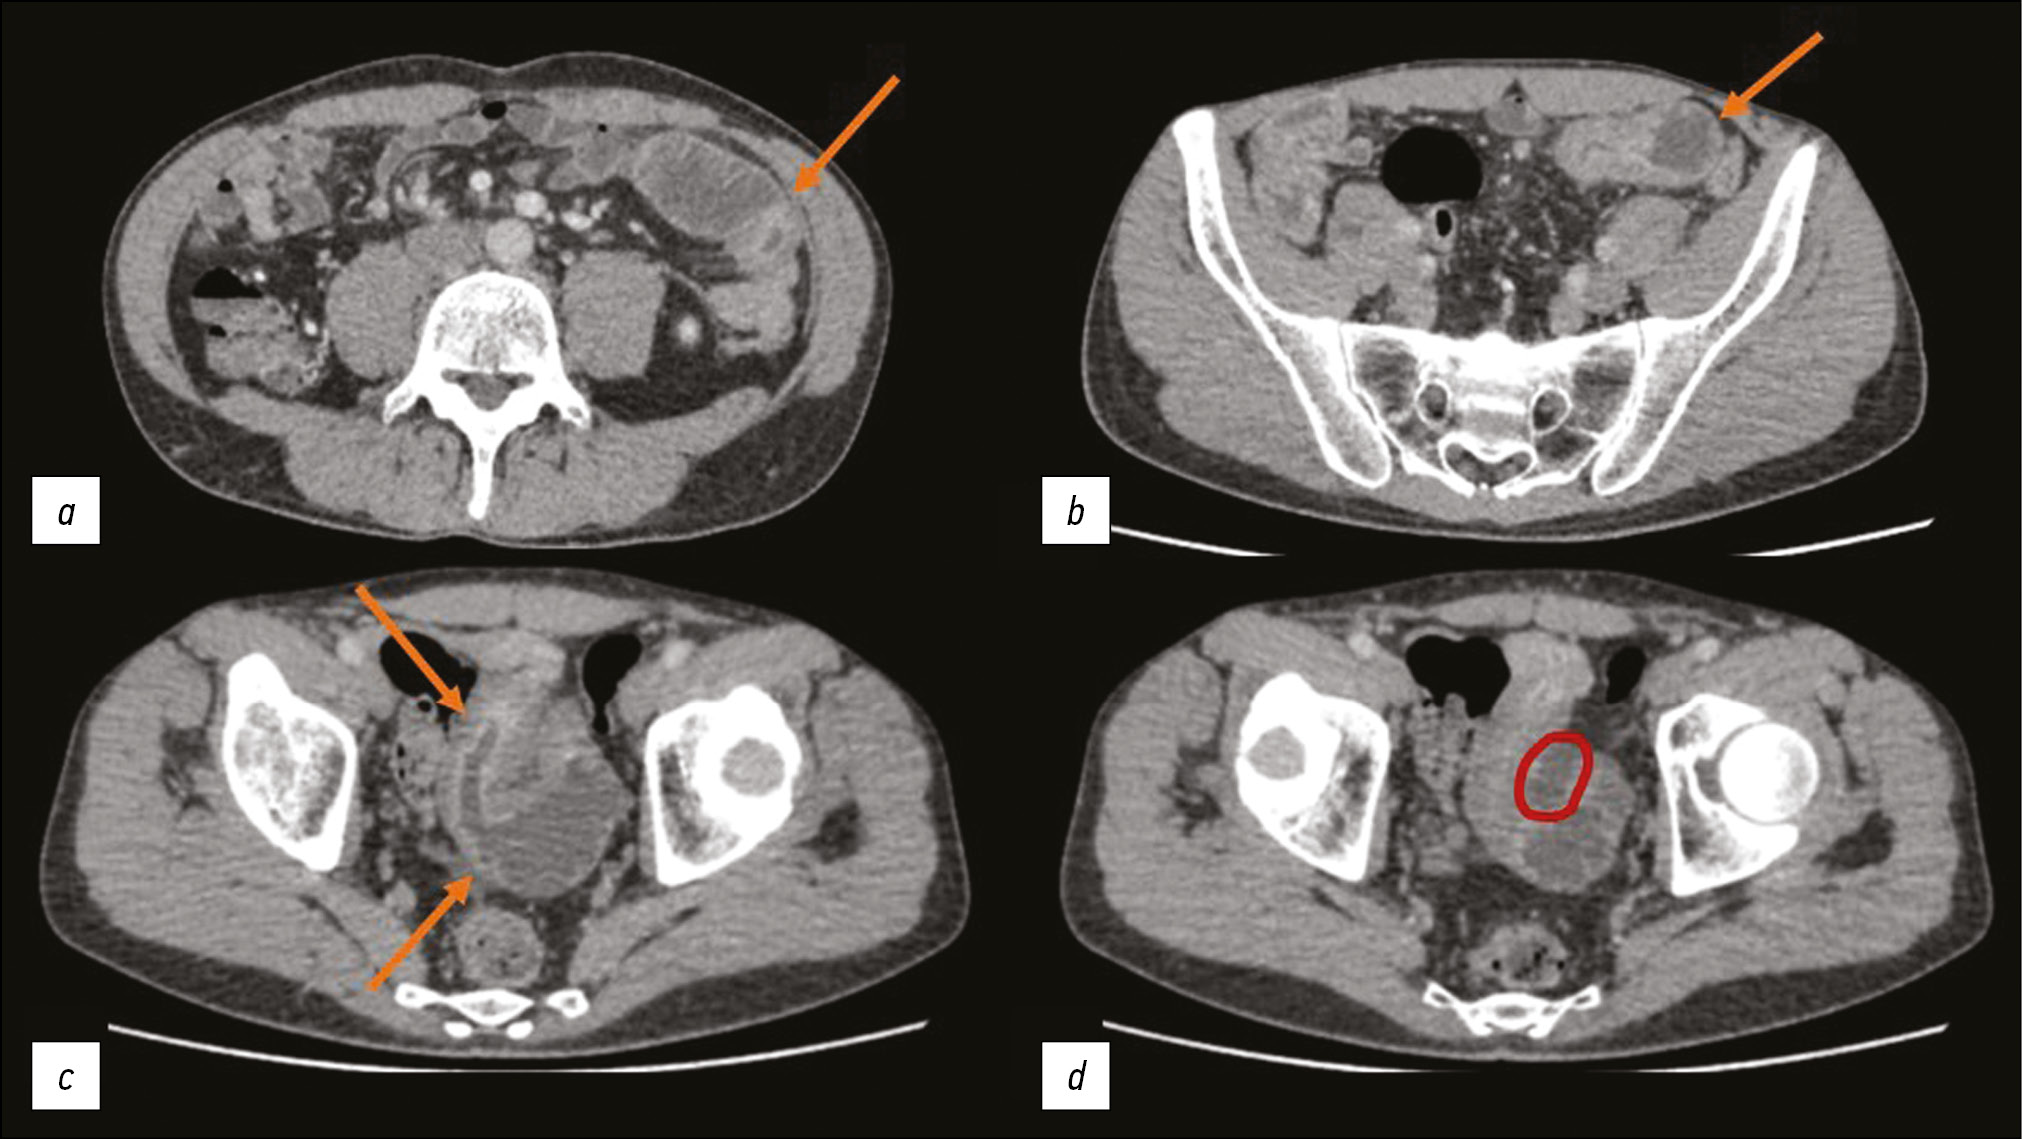

Abdominal MSCT with intravenous contrast was performed after the oral administration of 1 L of macrogol solution. The jejunum and ileum walls were locally thickened with inactive contrast agent accumulation. Approximately 5 cm of the wall of the distal jejunum transitioning into the ileum was markedly thickened up to 17 mm, with more active contrast agent accumulation, including in the mucosa (Fig. 1). Regional adipose tissue was infiltrated with the formation of liquid zones along the midline between the loops in the small pelvis; and regional lymph nodes as large as 9 mm showed active accumulation of the contrast agent.

Fig. 1. Abdominal multislice computed tomography with intravenous contrast, axial plane: a) substantial narrowing of the intestinal lumen and thickening of the wall with active contrast agent accumulation (arrow); b) dilated loop of the small intestine with an unevenly thickened wall (arrow); c) dilation and narrowing of the intestinal lumen is visible; additionally, of interest is the intestinal mucosa, which actively accumulates the contrast agent (arrows); d) the area of fluid accumulation between the loops in the small pelvis is marked red.